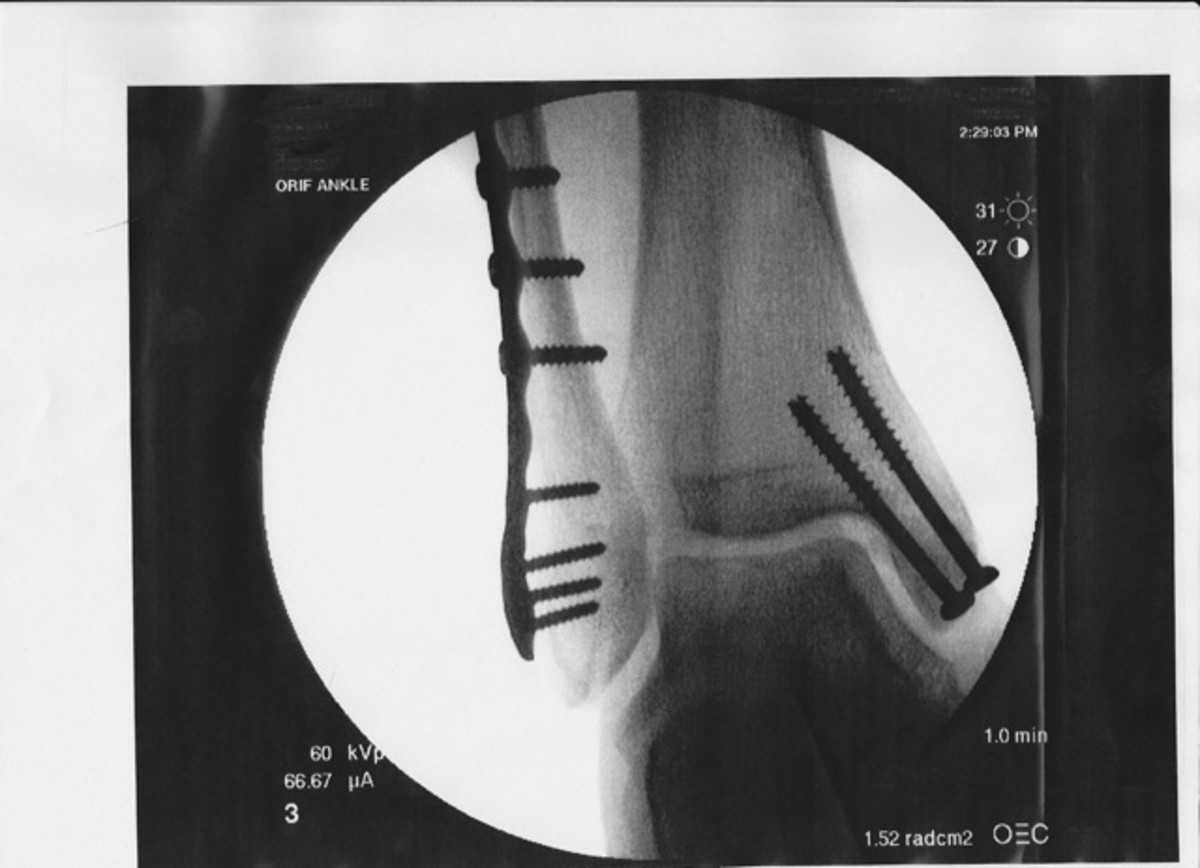

Screw Removal From Ankle . This can be done in the office or with mild sedation (twilight sleep) in. What is metalwork used for? After my recovery, i had to make a decision: E can include plates, screws, wires, rods and staples. Following surgery, a bandage and a cam boot will be fitted. You've had surgery to remove orthopedic hardware such as metal screws, pins, or plates. Many foot and ankle procedures require insertion of metal plates, screws, rods, or similar implants for stabilization of the bones while they heal. External fixators (pins and bars outside the skin) are routinely removed. When i broke my ankle, the repair involved inserting a plate and screws. You can expect some pain and swelling around. Ankle fracture plate and screw rehab.

You've had surgery to remove orthopedic hardware such as metal screws, pins, or plates. Many foot and ankle procedures require insertion of metal plates, screws, rods, or similar implants for stabilization of the bones while they heal. This can be done in the office or with mild sedation (twilight sleep) in. What is metalwork used for? Ankle fracture plate and screw rehab. External fixators (pins and bars outside the skin) are routinely removed. Following surgery, a bandage and a cam boot will be fitted. After my recovery, i had to make a decision: When i broke my ankle, the repair involved inserting a plate and screws. E can include plates, screws, wires, rods and staples.